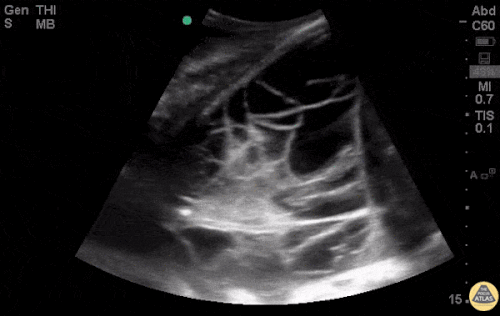

CEllulitis - CobbleStoning

Abscess

Evidence: https://bmjopen.bmj.com/content/7/1/e013688

Tutorial: http://5minsono.com/softtissue/